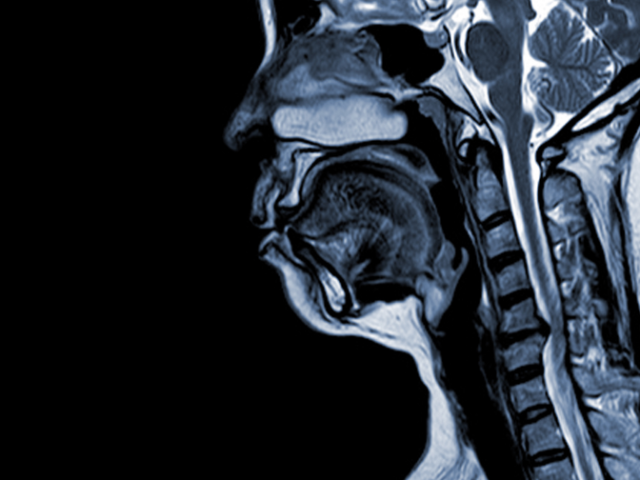

De la simptom la diagnostic: cum se investighează corect o suspiciune de tumoră cerebrală?

Apariția unor simptome neurologice poate fi un moment dificil pentru pacient. Durerile de cap persistente, tulburările de vedere, episoadele de pierdere a echilibrului, dificultățile de vorbire sau slăbiciunea apărută pe o parte a corpului ridică, firesc, multe întrebări. Totuși, aceste manifestări nu înseamnă automat existența unei tumori cerebrale. Ele indică, mai degrabă, nevoia unei evaluări…